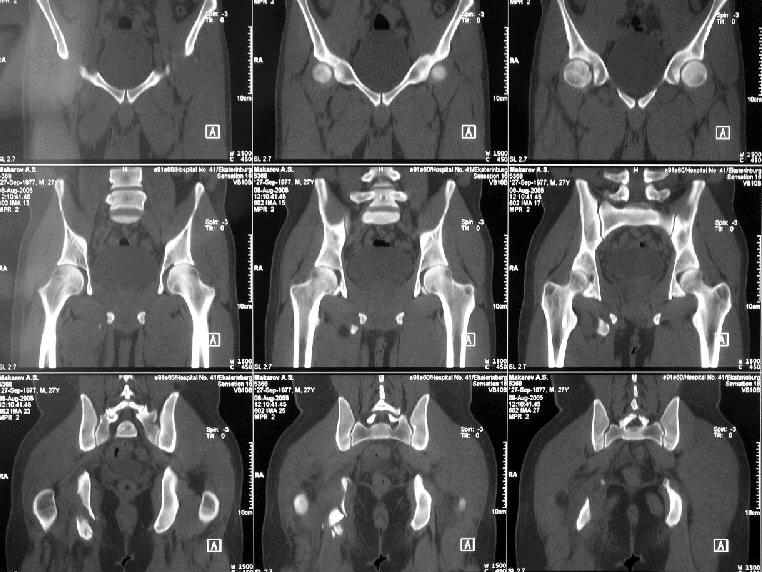

Уважаемые коллеги, хотелось бы услышать ваше мнение по тактике лечения следующего пациента: мужчина, 27 лет, получил травму на производстве 25 июня - перелом правого седалищного бугра (кт и рентгенограмма прилагаются).

Больной жалуется на боли - сидя и при ходьбе. В настоящее время ходит, хромая, без дополнительной опоры. Оторвавшийся седалищный бугор состоит из 2-х фрагментов, один из которых раздражает седалищный нерв. Если кто-то имеет опыт оперативного лечения подобных повреждений, подскажите из какого доступа лучше это сделать. Заранее спасибо.